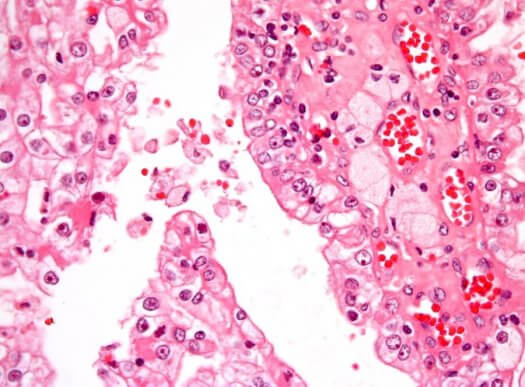

Kræft opstår når ondartede celler deler sig ukontrollerbart i kroppen. Den hyppigste form for nyrekræft i barndommen kaldes Wilms tumor eller nefroblastom. Den er robust, og tager form i det umodne nyrevæv.